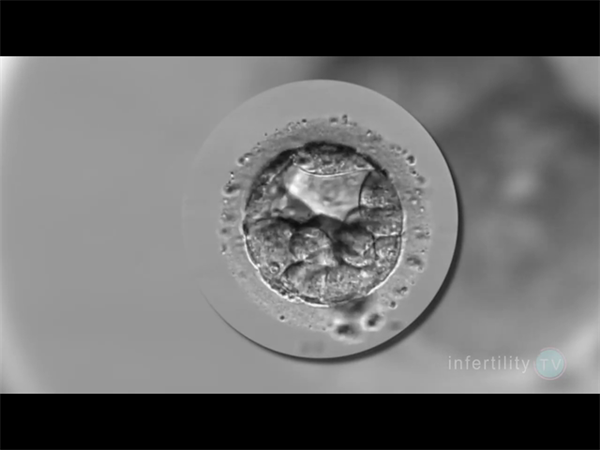

囊胚筛查主要包括三种类型的检测,PGT-A筛查胚胎的染色体数目是否正常,即非整倍体遗传学筛查;PGT-M针对特定的单基因遗传病进行筛查,例如色盲、血友病等;PGT-SR筛查染色体结构变异,例如平衡易位或者罗氏易位,其在一定程度上能减少宫外孕和胎停的可能性。但它们并不能保证筛查完全覆盖所有可能的遗传疾病,特别是当这些基因突变属于未知或新的遗传疾病时。

尽管囊胚筛查(如PGS/PGD)能够检测染色体异常和单基因遗传病,但其成功率并非100%。单基因遗传病的种类繁多,目前已知有7000多种单基因遗传病,其中4000多种已明确致病基因。因此,即使囊胚筛查正常,也不能完全排除其他未检测到的单基因遗传病。目前的基因筛查技术主要针对已知的遗传病基因进行检测,如地中海贫血、唐氏综合症等。然而,许多隐性遗传病可能尚未被完全识别或列入筛查范围。即使使用全基因组测序(NGS)技术,也无法检测到所有潜在的基因突变。